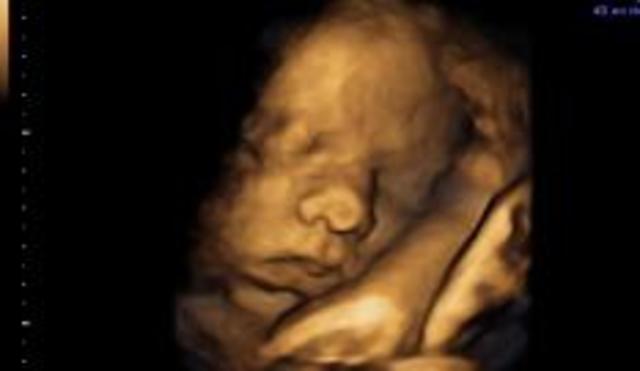

• 12 Semana de Gestación

12 Semana de Gestación

En los rasgos externos la cabeza está erecta, el cuello está casi recto y bien definido, también el oído externo adopta su forma y se ha desplazado casi a su posición definitiva en la cabeza

• Period: to

12 SDG

El saco vitelino se ha retraído, el feto deglute líquido amniótico y puede responder a la estimulación de la piel, los ovarios descienden por debajo del reborde pélvico, también se produce la hormona paratiroidea y la sangre se puede coagular